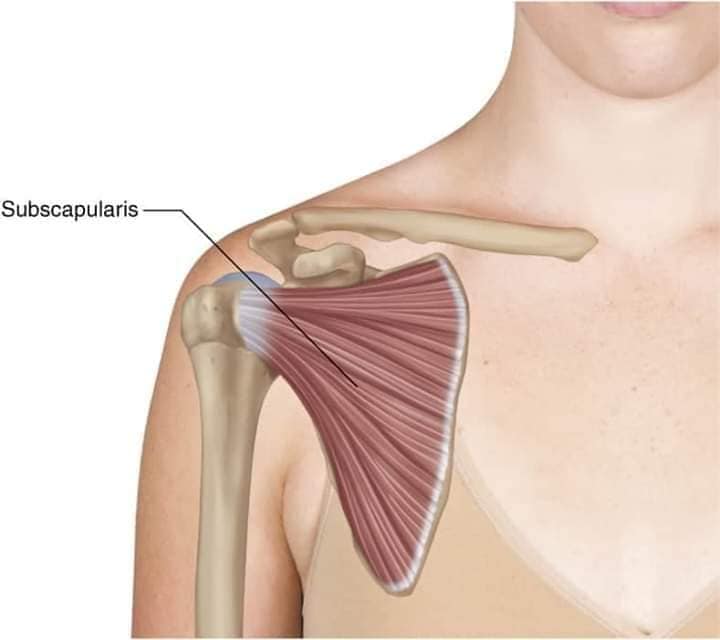

М'язова система людини є однією з основних систем організму, що відповідає за рухи, підтримання пози та стабільність. Вона складається з понад 600 м'язів, які можна класифікувати на скелетні, гладкі та серцеві м'язи. Скелетні м'язи, які є об'єктом нашого детального розгляду, дозволяють контролювати навколишній світ і виконувати різноманітні рухи. Особливу увагу в нашій статті буде приділено шейним і спинним м'язам, оскільки ці групи м'язів мають критичне значення для підтримання правильного постава та функціонування хребта.

М'язи, що піднімають лопатку: Трапецієподібний м'яз: великий м'яз, що покриває верхню частину спини. Його функція - підтримка і рух лопаток, а також забезпечення стабільності хребта.

М'язи, що ведуть лопатку до хребта: Широкий м'яз спини: великий м'яз, що розташований в нижній частині спини. Він відповідає за рухи плечей і лопаток, а також за розширення верхньої частини тулуба.